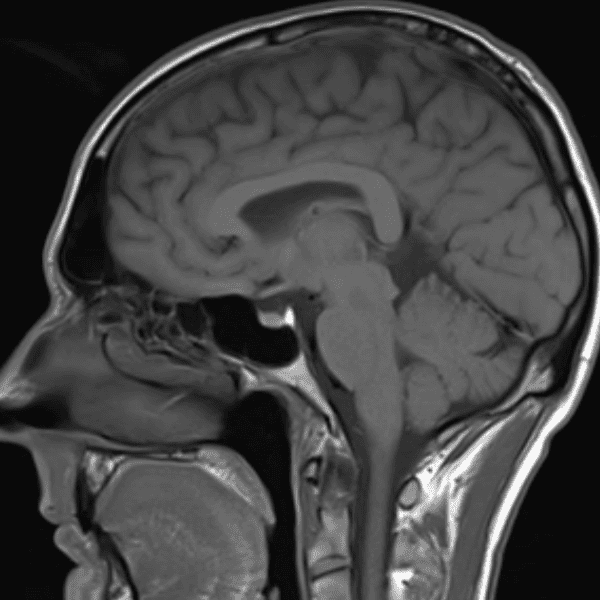

๋ฏธ๋ฌ˜ํ•˜๊ฑฐ๋‚˜ ์–ด๋ ค์šด ์‚ฌ๋ก€์™€ ์ผ๋ถ€ ์ •์ƒ ์‚ฌ๋ก€๋ฅผ ํฌํ•จํ•˜์—ฌ ๋‹น์ง์„ ์‹œ๋ฎฌ๋ ˆ์ด์…˜ํ•ฉ๋‹ˆ๋‹ค.

50 ์‚ฌ๋ก€